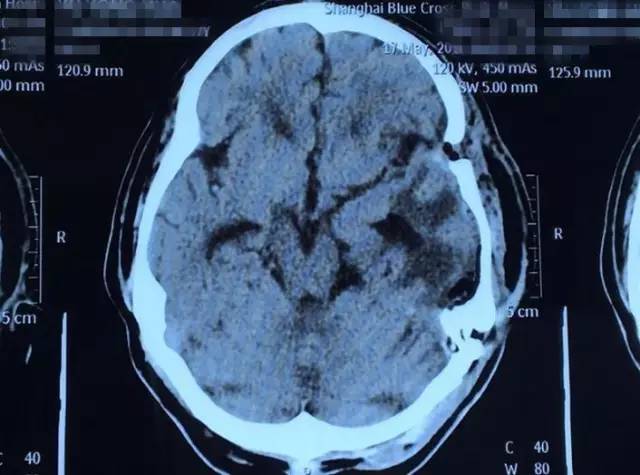

这名患者叫虞文军(化名),57岁,浙江宁波人。三个月前虞文军右侧手臂肘部至肩部出现酸痛,上举无力,持续时间不长后缓解,因此便没在意。半个月前,虞文军在开车时再次突然出现手臂酸痛无力症状,致使方向盘失去控制发生车祸连撞三车,所幸并无人员伤亡。虞文军这才意识到问题的严重性,至当地医院就诊,行头颅CT检查示:左侧颞区底部大脑凸面可见类圆形略高密度占位病变,周围见低密度水肿影,CT值为44HU,大小约为8*6cm,周边脑组织及脑室受压,中线结构右移,额顶部软组织肿胀,考虑为左侧底部脑膜瘤。

术前影像资料:红圈内白色部分为肿瘤物

术后影像资料:白色肿瘤物消失